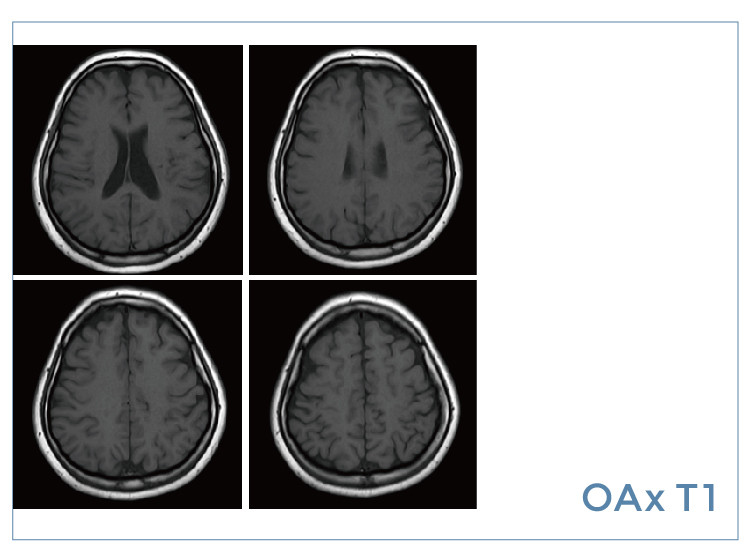

【朗润影像档案】磁共振影像病例分享(编号20190823)